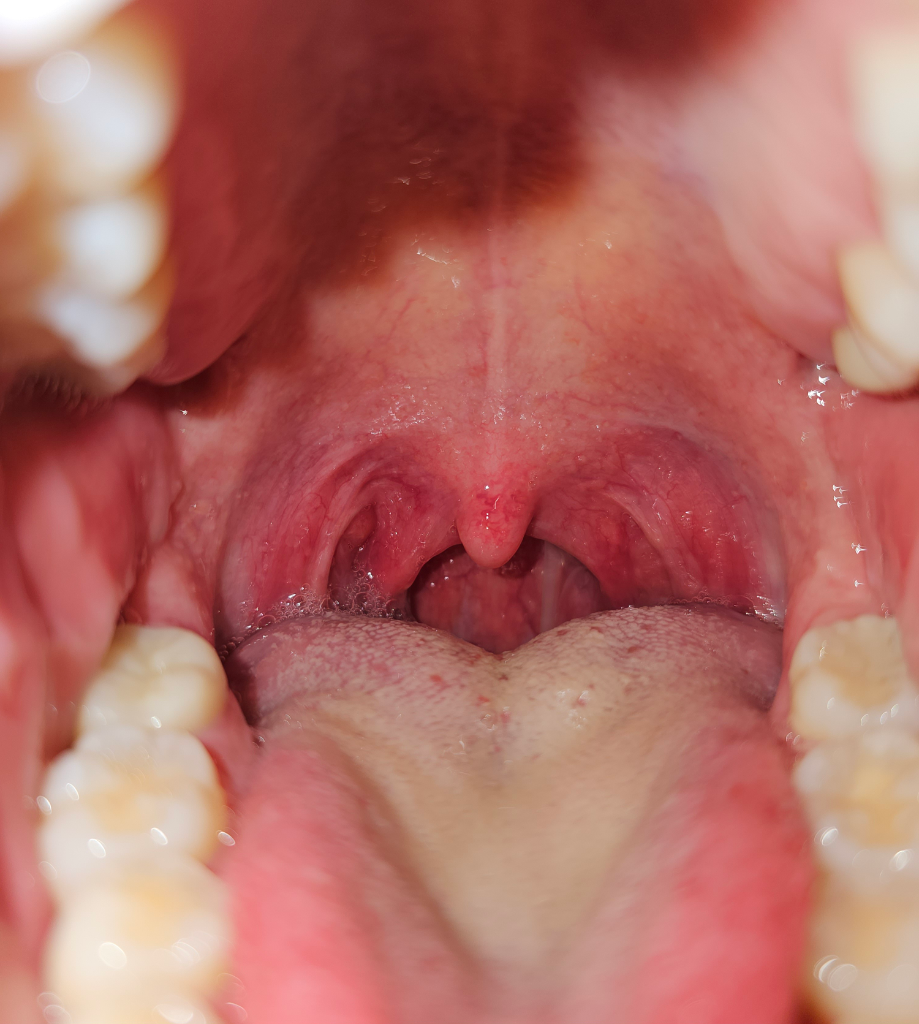

편도부종이 심해보이지는 않고 인후염 (Pharyngeal injection )은 있어보입니다.증상이 지속된다면 내과 혹은 이비인후과에 방문하셔서 현재 악화되고 있는 증상에 대해 면밀한 병력청취와 신체진찰을 받으시고 적절한 조치와 처방을 받으시는 것을 권해드립니다.

한쪽 편도만 부어있어도 편도염에 해당합니다. 그렇지만 해당 내용만 보고 인후통 증상이 있으므로 편도염이다 어떻다 판단할 근거가 되지 않습니다. 구체적인 감별 진단을 위해서는 병원에 가보아야 합니다.